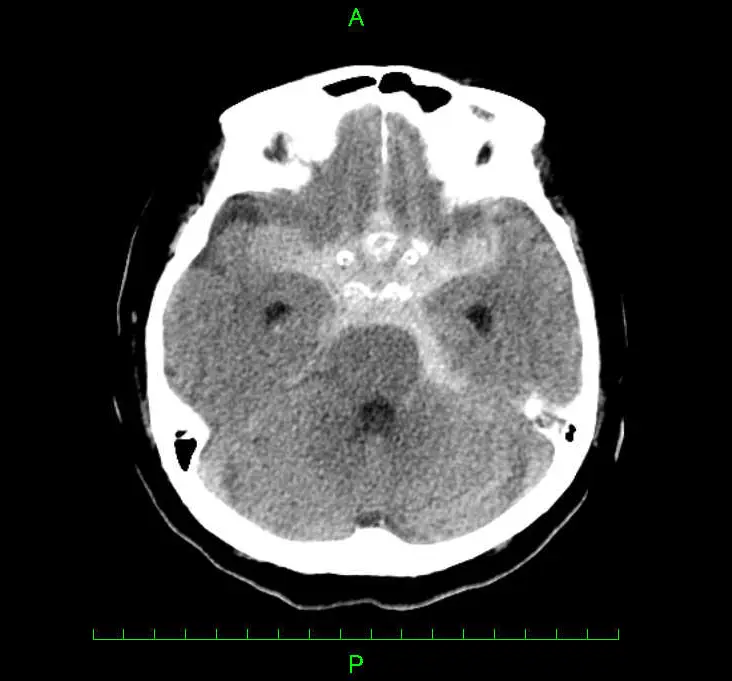

くも膜下出血(くもまくかしゅっけつ、クモ膜下出血)とは、脳出血(頭蓋内出血)の一種で脳を覆うくも膜と脳の間に出血が起きる状態を呼びます。発生頻度は比較的低い病気ですが、ひとたび発症すると死に至る確率も高く、助かった場合も重篤な後遺症が残る可能性が高いとされています。原因はほとんどの場合、脳の動脈にできたこぶ(脳動脈瘤)の破裂によるものです。

頭部CT検査を用います。CTでくも膜下出血と診断された場合は、原因の特定等を目的に造影検査やMRI検査などを行います。